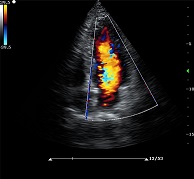

? ? ? ?C7為深圳安盛生物醫(yī)療技術(shù)有限公司新一代便攜式彩超產(chǎn)品,采用了先進(jìn)的PC平臺(tái),擁有強(qiáng)大的處理能力,優(yōu)異的圖像性能,集小巧輕便、全面的功能與輕巧流暢、特有的U型設(shè)計(jì)與一身,提供大眾新選擇。

? ?● 多種成像模式

? ? ? ?B、C、PW、CW、BCD三功、大角度偏轉(zhuǎn)成像、實(shí)時(shí)寬景成像、梯形成像(僅支持線(xiàn)陣)、解剖M型、彩色M型成像、組織多普勒成像、3D/4D成像

? ?● 彩色多普勒增強(qiáng)技術(shù)

? ? ? ?有效抑制彩色血流閃動(dòng)噪聲,提高血流分辨率和靈敏度